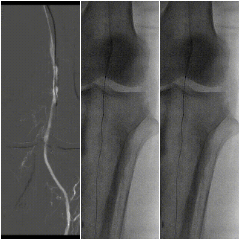

右股总-髂外闭塞,左股-腘动脉全程闭塞,膝下流出道显示不清,重度钙化

图:术前CT

图:造影显示,股腘动脉全程闭塞,膝下流出道差